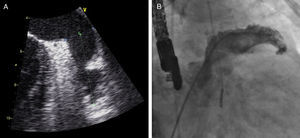

Após se satisfazerem todos estes critérios de bom posicionamento, o dispositivo foi libertado e realizou-se nova avaliação fluoroscópica e ecocardiográfica (Figura 4) para avaliar eventuais complicações imediatas, como deslocamento ou migração do dispositivo, formação de trombo intracardíaco ou adjacente ao dispositivo, derrame pericárdico, compressão da artéria circunflexa ou da veia pulmonar superior esquerda, ou a presença de fluxo residual. No caso de estes critérios não se encontrarem satisfeitos, o dispositivo deveria ser total ou parcialmente recapturado e reposicionado antes de ser libertado.

Foi mantida vigilância clínica em regime de internamento até 24h após o procedimento, para vigilância de complicações relacionadas com o acesso vascular, hemorragias, estabilidade hemodinâmica. Foi realizado ecocardiograma transtorácico no primeiro dia após encerramento para avaliação de derrame pericárdico, deslocamento ou migração do dispositivo, fluxo peridispositivo ou formação de trombo aderente ao mesmo.

Complicações durante o seguimentoNo ecocardiograma transesofágico de controlo realizado um mês após o encerramento percutâneo do AAE, foi identificado em um doente um trombo atapetando a face auricular do dispositivo ACP. Nessa altura, foi substituída a dupla antiagregação em curso por enoxaparina na dose de 1mg/kg de 12-12h. Foram também intensificados os controlos por ecocardiograma transesofágico: uma semana depois, documentando regressão ligeira do trombo, posteriormente com periodicidade mensal até aos 6 meses de seguimento, altura em que foi verificada regressão quase completa do trombo. Tendo em conta os antecedentes de hemorragia severa sob hipocoagulação oral com INR terapêutico, foi retomada antiagregação simples. Nessa altura foram realizados estudos de trombofilia e autoimune, que foram negativos. Três meses depois, o doente apresentou anemia subaguda sem perdas hemáticas evidentes, tendo sido feito um estudo no decurso do qual foi diagnosticada uma neoplasia do cólon submetida a cirurgia e a quimioterapia. No ecocardiograma transesofágico realizado 12 meses após a implantação do dispositivo não foi verificado trombo.

Foi apenas identificado um caso de fluxo peridispositivo, que, contudo, apresentava uma largura de jato de cor < 3mm (ligeiro de acordo com a classificação de Ostermayer e et al.26). Este foi visualizado no ETE do primeiro mês, realizado para seguimento de um dispositivo WATCHMAN.